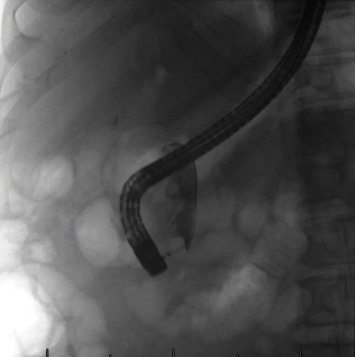

The patient underwent an outpatient ERCP with the successful removal of large amounts of food material, sludge, and white stones from the bile duct using a 15 mm balloon (Figures 2 and 3). During ERCP, the prior sphincterotomy was noted to be stenosed and a biliary sphincterotomy was performed. There was no duodenal diverticulum seen during ERCP. No further imaging such as endoscopic ultrasound or magnetic resonance cholangiopancreatography (MRCP) was obtained prior to ERCP due to the likely culprit of debris in the CBD stump seen on CT imaging, and the dual benefit of imaging and treatment that ERCP affords.